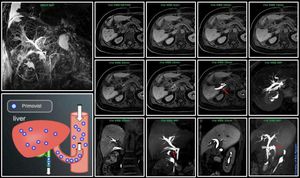

MR Abdominal Imaging – The Art of Primovist/Eovist beyond focal liver lesions characterisation @ Siemens 1.5T Aera Besides focal liver lesions characterisation, you can use Primovist for answering the question regarding bile duct leakage. How is this possible? After injection of Primovist, approximately 50% of the administered dose in the normal human liver is transported through the hepatocytes and excreted into the bile. If there is a leakage, this contrast agent can provide that information. In this case, there is a leakage (red arrow).#Siemens_MRI #siemens #mri #primovist #bile_duct_leakage